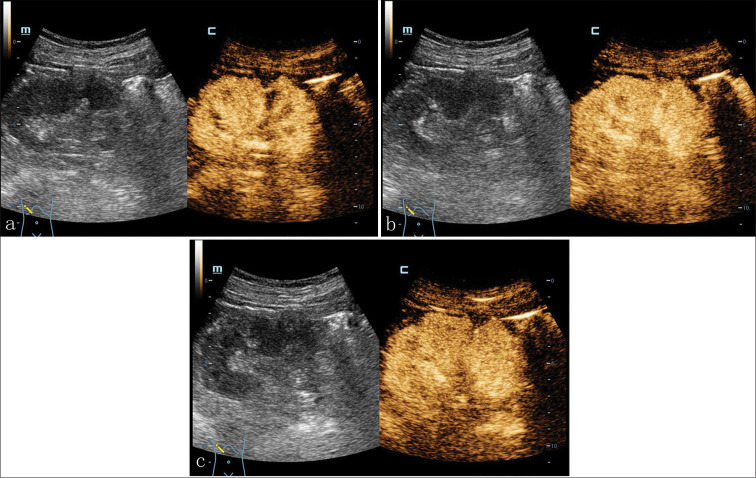

我们报告了一例 71 岁男性肾小管囊性细胞癌(TRCC)患者的病例,这是一种罕见的肾肿瘤。患者因体检时发现右肾中极有一个囊性结节,经泌尿科超声检查后入院。该结节在常规超声检查中呈高回声,在对比增强超声检查中,增厚的囊壁在峰值相的增强强度与肾实质相似。计算机断层扫描血管造影显示肿瘤呈异质性对比增强,磁共振成像显示 T1 加权成像(WI)呈低密度,T2WI 呈高密度。组织学上,海绵表面由典型的管状和多房囊性成分组成,内衬单层上皮细胞。最终病理诊断为 TRCC。患者顺利地接受了腹腔镜右肾根治术。患者出院后随访 12 个月,未发现局部或远处转移迹象。总之,TRCC 应根据放射学和组织学的综合结果进行准确诊断,以确保及时手术和更好的预后。

We present a case involving a 71-year-old male with tubulocystic renal cell carcinoma (TRCC), which is a rare entity of renal neoplasm. The patient was admitted for a cystic nodule on the middle pole of the right kidney by urological ultrasound during physical examination. The nodule presented with hyperechoic on conventional ultrasonic and the enhancing intensity of thicken cystic wall at the peak phase in contrast-enhanced ultrasound was similar to that of the renal parenchyma. Findings from computed tomography angiography exhibited heterogeneously contrast enhancing tumor, and magnetic resonance imaging demonstrated hypointense on T1-weighted images (WI) and hyperintense on T2WI. Histologically, the spongy surface was composed of the typical tubular and multiloculated cystic components lined by a single layer of epithelial cells. The final pathological diagnosis was TRCC. The uneventful laparoscopic right radical nephrectomy was conducted. The patient was followed up for 12 months after discharge and no signs of local or distant metastasis were found. In conclusion, TRCC should be accurately diagnosed on the basis of comprehensive radiological and histological findings to ensure a timely surgery and better prognosis.